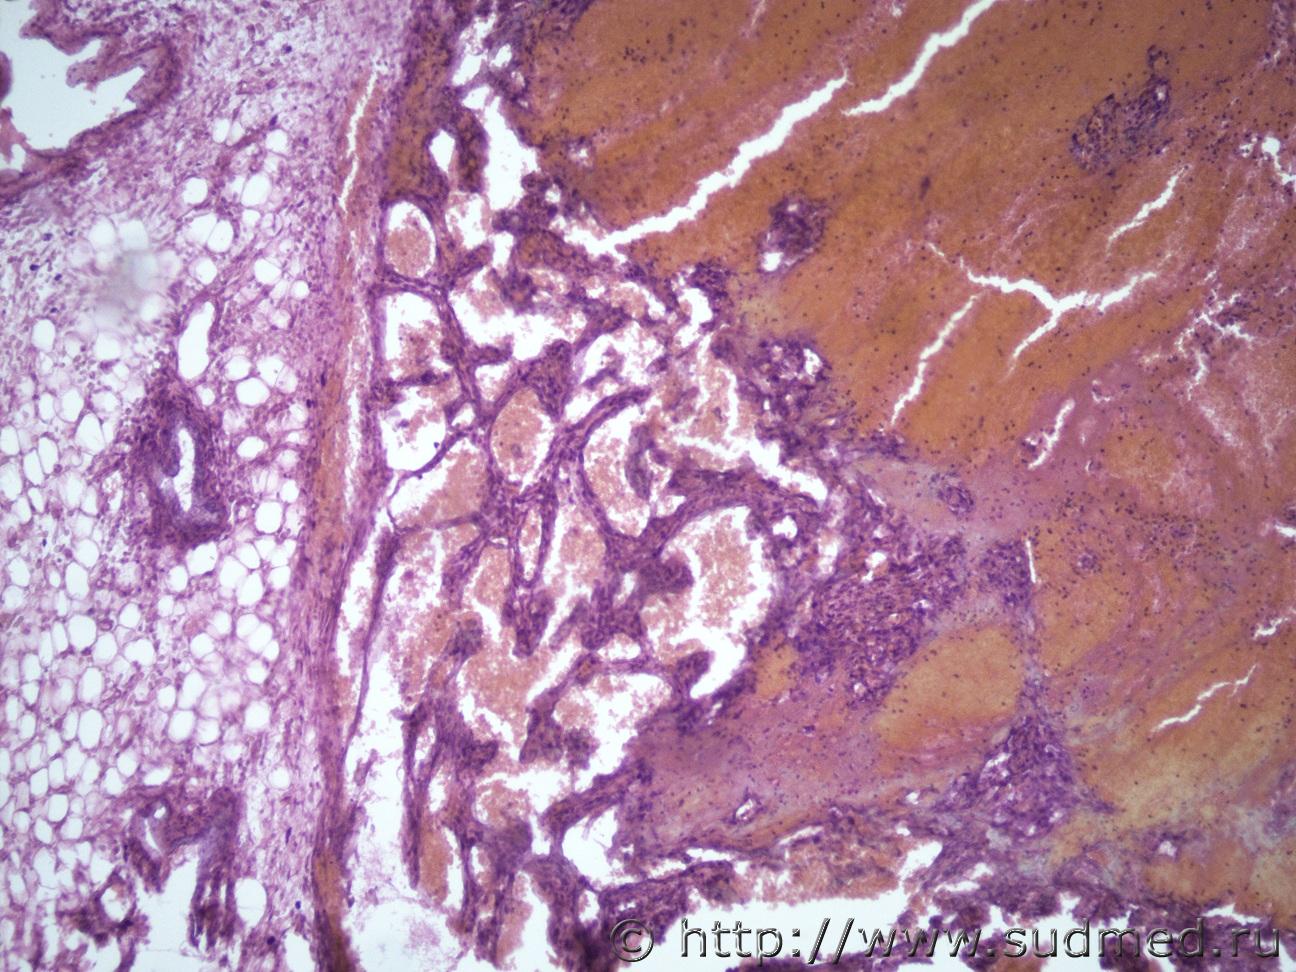

Ув. коллеги, может это тема не для нашего форума, но вдруг у кого нибудь будут идеи по этому поводу. В течении месяца выросло образование за ухом у лабораторной крысы округлой формы, плотно-эластической консистенции, в диаметре 1 см. Хозяин крысы подумал, что это абсцесс и решил сделать пункцию, после прокола истекло приличное количество крови и в течении 10-20 мин крыса скончалась. Макро- образование округлой формы, в тонкой капсуле, строма в виде ячеек, с кровоизлияниями.Судебная медицина - Прикрепленное изображение Судебная медицина - Прикрепленное изображениеСудебная медицина - Прикрепленное изображениеСудебная медицина - Прикрепленное изображениеСудебная медицина - Прикрепленное изображение

Похоже на кавернозную гемангиому .

Я тоже об этом подумала, но как она выросла за 1 мес, достаточно внушительных размеров для грызуна.